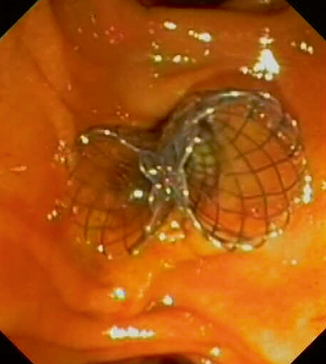

Fig. 8.3

Endoscopic view of two self-expandable metal stents

Multiple SEMS placement is performed for palliation of complex malignant hilar strictures. This procedure is quite different from single SEMS placement. After selective opacification and cannulation of the intrahepatic ducts above the complex stricture, two to four guidewires are placed through the stricture deeply into the intrahepatic ducts that should be drained. Every metal stent is released under endoscopic and fluoroscopic control and “side-by-side” over the previously placed guidewires. It is advisable to release the stents trans-papillary in order to facilitate future re-interventions for SEMS occlusion (Fig. 8.3). Another reported technique of deploying bilateral hilar metal stents is the stent-within-stent technique using large cell width SEMS [45]. This may be useful for patients with small extrahepatic bile duct diameter which would make deploying multiple SEMS adjacent to each other difficult. Guidewire access to typically the left biliary system is procured followed by SEMS placement into that duct. Wire access to this system is maintained while removing the stent delivery system and advancing an ERCP catheter over the wire. After pulling the wire back into the catheter, it is advanced into the other intrahepatic system by passing the wire in between the interstices of the first stent. The interstices must be dilated using a 4–8-mm hydrostatic balloon dilator or a Soehendra stent retriever. Then the second stent is advanced through the interstices of the first stent into position.

The number of stents that should be placed is usually chosen according to the complexity of the stricture. It is ideal although not always possible to place two SEMS for complete drainage of Bismuth type II stricture, three stents for type III, and three to four stents for type IV. In addition, SEMS for palliative treatment of malignant hilar strictures always must be uncovered in order to avoid occluding the side branches of the bile duct [26].